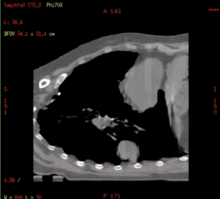

Smart D4D:胸部运动肿瘤4D成像